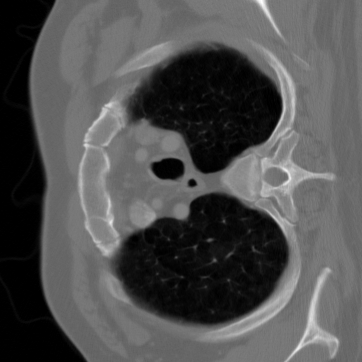

本项目用于医学CT图像重建与去噪优化,针对低剂量CT图像噪声大、结构模糊的问题,设计基于Unrolled ADMM思想的深度重建网络,并结合C++/CUDA算子实现加速计算。适用于医学影像辅助分析、工业断层检测及图像重建优化场景。